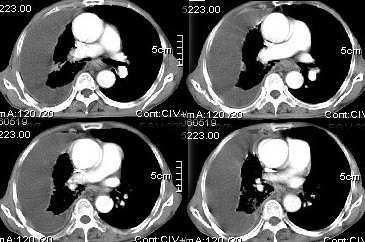

男,76岁,因心累,气紧加重,伴吐白色沫哝痰,偶尔有低烧,无盗汗。{门诊患者未见其它检查}

右肺上叶私有肿块,其内见条状 点状钙化,上叶后段支气管有阻塞征象,纵隔内见淋巴结影,大量胸水,陈旧性结核,肺癌不排除.

病灶在右上叶支气管的后段旁,成类圆形,约2.3厘米大小,其内见钙化密度区,病灶平扫为77,强化为87.左肺上叶尖后段沿血管支气管分布见小结节.我认为右上叶后段支气管开口有截断.我首先考虑是右中央型肺癌伴右恻大量胸腔积液,但左肺的病变我真的有的不好解释,希望各位战友继续讨论,不对之处望指出!!谢谢!!!

右肺毁损萎陷,其内可见钙化灶、残存空腔及支气管影。左上叶可见多发小结节影。纵隔左移,其内未见肿大淋巴结。右侧胸腔大量积液。考虑:肺结核并右肺毁损;右侧胸腔大量积液。

右侧大量胸腔积液伴右肺压迫性肺不张,上叶内是不是结核灶?

右肺萎陷,上叶似有肿块,其内见条状、点状钙化,上叶后段支气管有阻塞征象,纵隔内见肿大淋巴结影,右侧大量胸水,陈旧性结核。同时不排除在原有双肺结核的基础上出现右上肺癌并胸膜及纵隔淋巴转移的可能

支持右肺ca伴胸水,依据1有点状钙化肿块2支气管截断。最好抽胸水后再扫描,支气管镜检最好。

右上叶后段开口处可见约3cm·3cm大小的肿块,边缘较光滑,无明显分叶且有钙化,右上叶支气管后壁受侵不明显,加上左上叶病灶。我首先考虑肺结核,胸腔积液。右肺不张。还是建议支气管镜检查,或者胸水检查。

一看这个病人的定位片大致倾向恶性病变,因胸水漫顶,纵隔少偏.右上肺门旁肿块肯定,肺内肿瘤可能性很大.右上肺病灶多为陈旧性结核.实际上结核病并发肿瘤并非少见.所以二元论诊断也不奇怪.

右后段处示一肿块但无明显肺癌强化方式,其内尚见钙化,胸膜亦无结节样增厚,再加上左肺结核表现(支血束结节样增粗不确切),则更支持结核伴大量胸液表现。